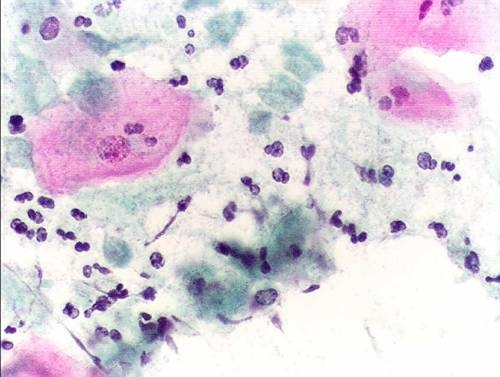

Tinción de Papanicolau de una muestra infectada por 'Trichomonas vaginalis'. (Foto: Alex_brollo)